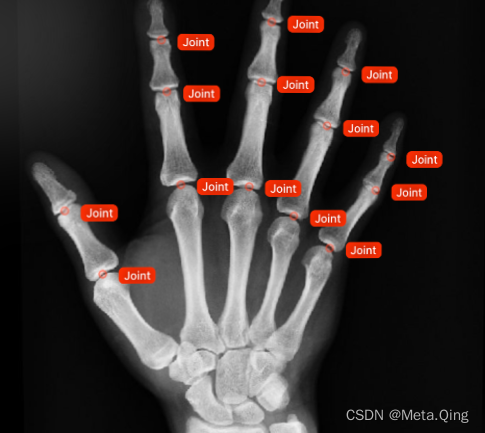

医学图像注释是标记医学成像数据的过程,例如 X 射线、CT、MRI 扫描、乳房 X 光检查或超声波。

它用于训练用于医学图像分析和诊断的 AI 算法,帮助医生节省时间、做出更明智的决策并改善患者治疗效果。

医学图像注释是标记医学成像数据的过程,例如 X 射线、CT、MRI 扫描、乳房 X 光检查或超声波。

它用于训练用于医学图像分析和诊断的 AI 算法,帮助医生节省时间、做出更明智的决策并改善患者治疗效果。

在这两个示例中,通常需要多个视图来评估正在发生的事情。例如,手部的 X 光片可能仅在手部处于特定姿势或角度时才显示骨折。

尽管如此,捕捉手的正面视图是标准的。

手的正面视图。

第 3 和第 4 中节指骨基底部的小骨折大多仅在右图可见。